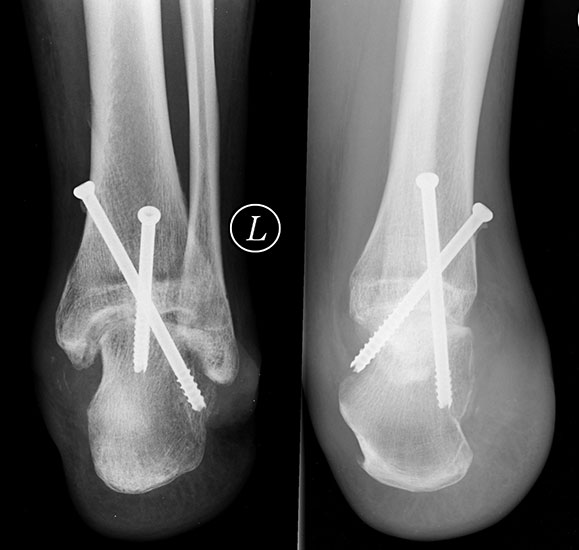

Als Komplikation von Lisfranc- Amputationen werden regelmäßig postoperative Equinovarus-Fehlstellungen beobachtet. Dies lässt sich durch eine transossäre Reinsertion der Peroneal­sehnen und, falls nötig, Verlängerung der Achillessehne sowie konsequente postoperative Redression in einem Gips vermeiden. Ist ein plantigrades Auftreten gesichert, so können Patienten nach Amputationen in der Lisfranc-Linie teilweise auch ohne Prothese auskom­men. Durch einen flachen Schuh mit harter Sohle und medialem Keilabsatz ist meist die Gehfähigkeit mit nur unwesentlichen Einschränkungen gegeben 29.

Chopart-Amputationen neigen aufgrund des vollständigen Fehlens der Ansätze der Dorsal­extensoren und Pronatoren in noch größerem Maße zur Ausbildung einer Spitzfußstellung und Varuskontraktur (Abb. 15). Dies kann zu einer schlechteren Funktion als nach distalen Unterschenkelamputationen führen. Verhindert werden kann dies durch Reinsertion der Sehne des M. tibialis anterior und durch eine primäre Sicherung der Position durch einen tibiotalaren Fixateur externe oder sekundär durch eine Arthrodese des oberen und unteren Sprunggelenks. Als weiter proximal gelegene Amputationstechniken sind u. a. die Pirogoff-, Boyd- und Syme-Amputation beschrieben. Hierbei sind trotz osteoplastischer Modifikationen der einzelnen Techniken immer mehr oder weiniger große Beinlängendifferenzen zu erwarten 25. Bei der ursprünglichen Pirogoff-Amputation wird nach Talektomie das Tuber calcanei in die Malleolengabel geschwenkt und mit der Tibia fusioniert. Die Modifikation nach Boyd und Spitzy kann durch eine Vertikalisierung des lediglich im Bereich des Proc.anterior calcanei gekürzten Calcaneus eine geringere Beinverkürzung erzielen.